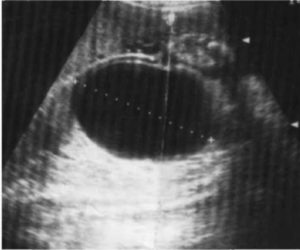

Мегацистисом называют увеличение у плода во время внутриутробного развития мочевого пузыря в продольном размере (больше 8 мм). Кроме этого увеличивается соотношение этого параметра к копчико-теменному размеру (составляет больше 10,4%, при норме — 5,4%). Мегацистис чаще всего обнаруживают на ранних терминах беременности (10-15 неделя) в 0,06-0,19% случаев.

На ультразвуковом исследовании мочевик визуализируется в виде грушевидного или округлого образования. Орган имеет тонкие стенки, расположен в нижней области туловища и увеличивается в размерах в течение беременности матери.

В некоторых случаях во время УЗИ диагностики у беременной женщины обнаруживается увеличенный мочевой пузырь у плода. Если размер органа увеличивается свыше 8 мм, то врач диагностирует о мегацистисе.

Кроме того, увеличенный мочевой пузырь встречается у детей во время внутриутробного развития. Как правило, диагноз мегацистис ставят на ранних сроках беременности. Встречается эта аномалия у 0,06% плодов. Об увеличенном мочевом пузыре (или, иначе, мегацистисе) говорят, когда продольный его размер превышает 8мм.